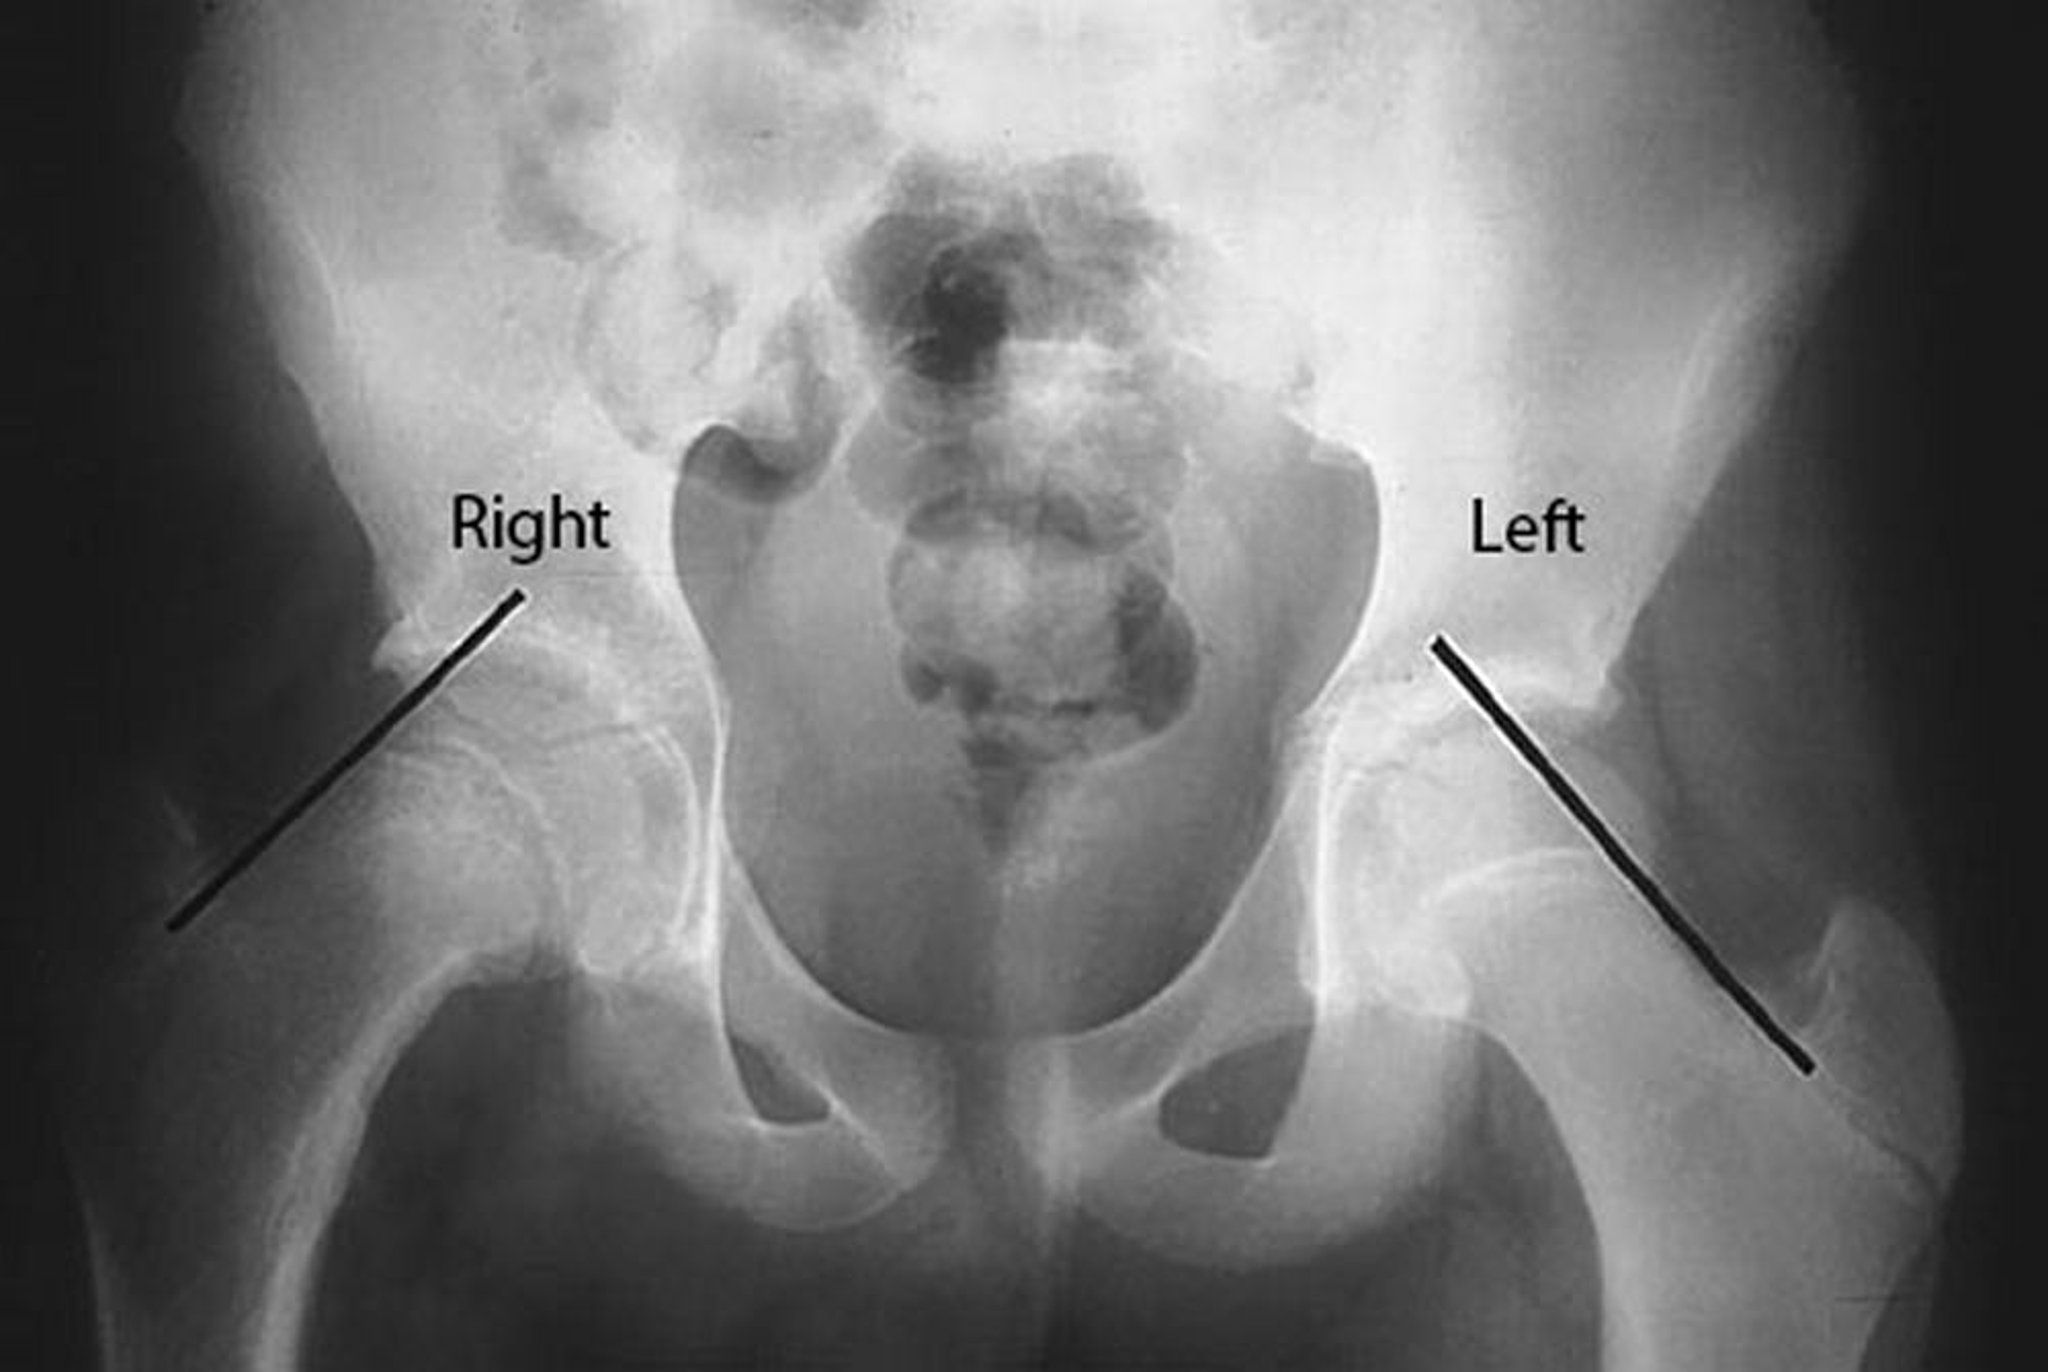

Линию Клейна проводят по верхней границе шейки бедренной кости у пациента с эпифезиолизом головки бедра (SCFE) правого бедра. Обратите внимание, что головка бедренной кости находится ниже линии Кляйна на пораженной правой стороне, в то время, как на здоровой стороне, слева, значительная часть головки бедренной кости расположена выше линии Кляйна.